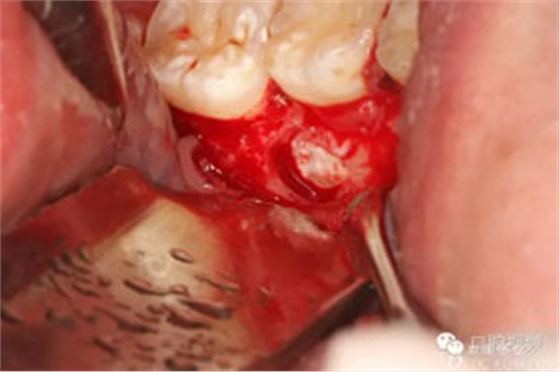

圖9.分牙、分別取出牙冠和牙根